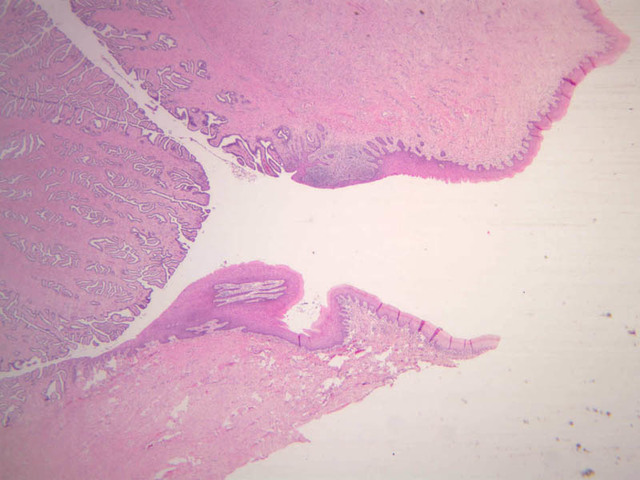

The resting or inactive mammary gland consists of predominantly dense connective tissue with small clusters of ducts and a few glandular elements (slide A-93 [2.5x-labeled, 10x, 20x, 40x] [1x, 2.5x, 10x, 20x]). It is difficult to differentiate between small ducts and alveoli as each is lined by simple low cuboidal cells. Lobes and lobules are not well defined. During puberty, predominantly under the influence of the ovarian hormone estrogen, the glandular or epithelial ducts proliferate and begin to differentiate into clusters of ductal and alveolar units termed terminal ductal lobule units (TDLUs). The non-pregnant gland will form multiple TDLUs that will not fully differentiate until pregnancy-induced growth. TDLUs are classified into Type I, Type II and Type III based on density of the ductules within each lobular unit. Type I and Type II lobules are typical of inactive glands that have not undergone a pregnancy cycle. Type III lobules are seen only in active glands or in inactive glands that have been through a pregnancy. Intralobular connective tissue is loose connective tissue that surrounds the alveoli and ducts within a lobule. The interlobular connective tissue is dense and contains considerable adipose tissue.

During pregnancy, predominantly under the influence of the ovarian hormone progesterone and the pituitary hormone prolactin, the glandular elements proliferate and differentiate to form milk-secreting units. In later stages of pregnancy, alveolar development becomes prominent and the amount of connective tissue and adipose tissue decreases. The secretory cells hypertrophy and accumulate secretory product.

The mammary gland in its active state is a compound tubuloalveolar gland (slide A-92 [10x, 20x, 40x-labeled] [2.5x, 10x, 20x, 40x]; A-94 [2.5x, 10x, 20x, 40x]). At this time, the gland is predominantly glandular tissue. Each alveolus is lined by a simple cuboidal epithelium. At the base of these cells, and within the alveolar basal lamina, are the stellate-shaped myoepithelial cells that are highly contractile and function to facilitate milk ejection.